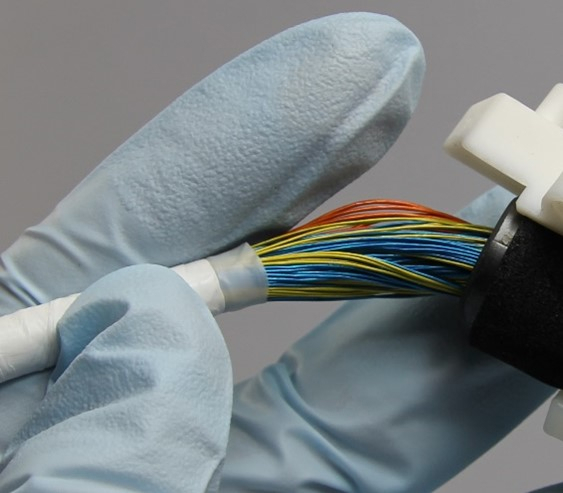

Inside your cable are hundreds of tightly bound wires. Each wire represents an element which together make up the entirety of your ultrasound image. If one or more of those wires is damaged, it can lead to black lines in your image referred to as dead elements. What this means is that the wire is now unable to transmit the signal from the probe head to the machine it is connected to and thus does not appear on your image.

Severe damage to your cable which exposes wires can also pose a risk to both yourself and your patient. Cable damage increases the risk of electrocution, cross-contamination and even infection.

While probes are designed to be water proof, damage to the cable can impair this ability and allow for fluid ingress. Cable insulation forms part of the electrical isolation between machine and person, if any wires are exposed this increases the risk of electrocution for both yourself and your patient.